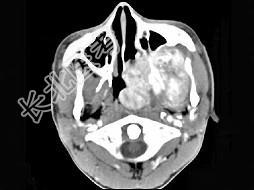

- 单项选择题男性,19岁, 左侧鼻腔反复出血一年余,CT、MRI扫描如图所示, 请选择最可能诊断 ( )

C、鼻咽部青年纤维血管瘤